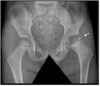

280

What parts of the body does Paget’s Disease “Osteitis Deformans” affect?

Affects pelvis, femurs, skull, tibias, vertebrae, clavicles, and ribs

281